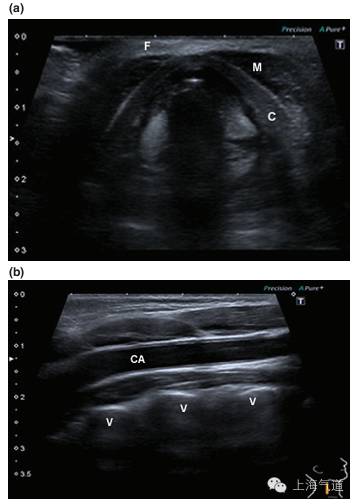

图1a. 将探头置于假声带水平取横断面超声影像,图中标识F为高回声的脂肪;M为低回声的肌肉组织,暗区内可见高亮的筋膜结构;C为低回声的软骨结构,其超声影像因其钙化程度而有差异,总体来说,回声较其周边的脂肪组织低。b.将探头置于右颈部取纵切面,CA为线性管状的颈动脉,其内为无回声的血液;V为颈椎椎体,超声很难穿过骨性结构,因此会在其表面形成高亮的反折线,其下形成伪影